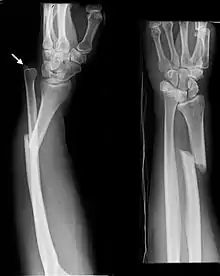

- Nightstick fracture is a fracture of the middle portion of the ulna without other fractures.[1]

An ulna fracture can be a single break as in a so called "nightstick fracture", which can be caused by someone being hit on the inside of the forearm often by a stick, notably when they are holding their arm up to protect their head from injury.[2][4] An ulna fracture can also result from falling on the forearm or falling on an outstretched arm.[2]

The term "nightstick fracture" originated from the notion that a person hit by a police truncheon would hold their arms up to protect their heads from injury. Historically they were treated without surgery, but this resulted in a high risk of the broken parts not joining properly, unless the broken parts were generally aligned and the skin intact.[7]